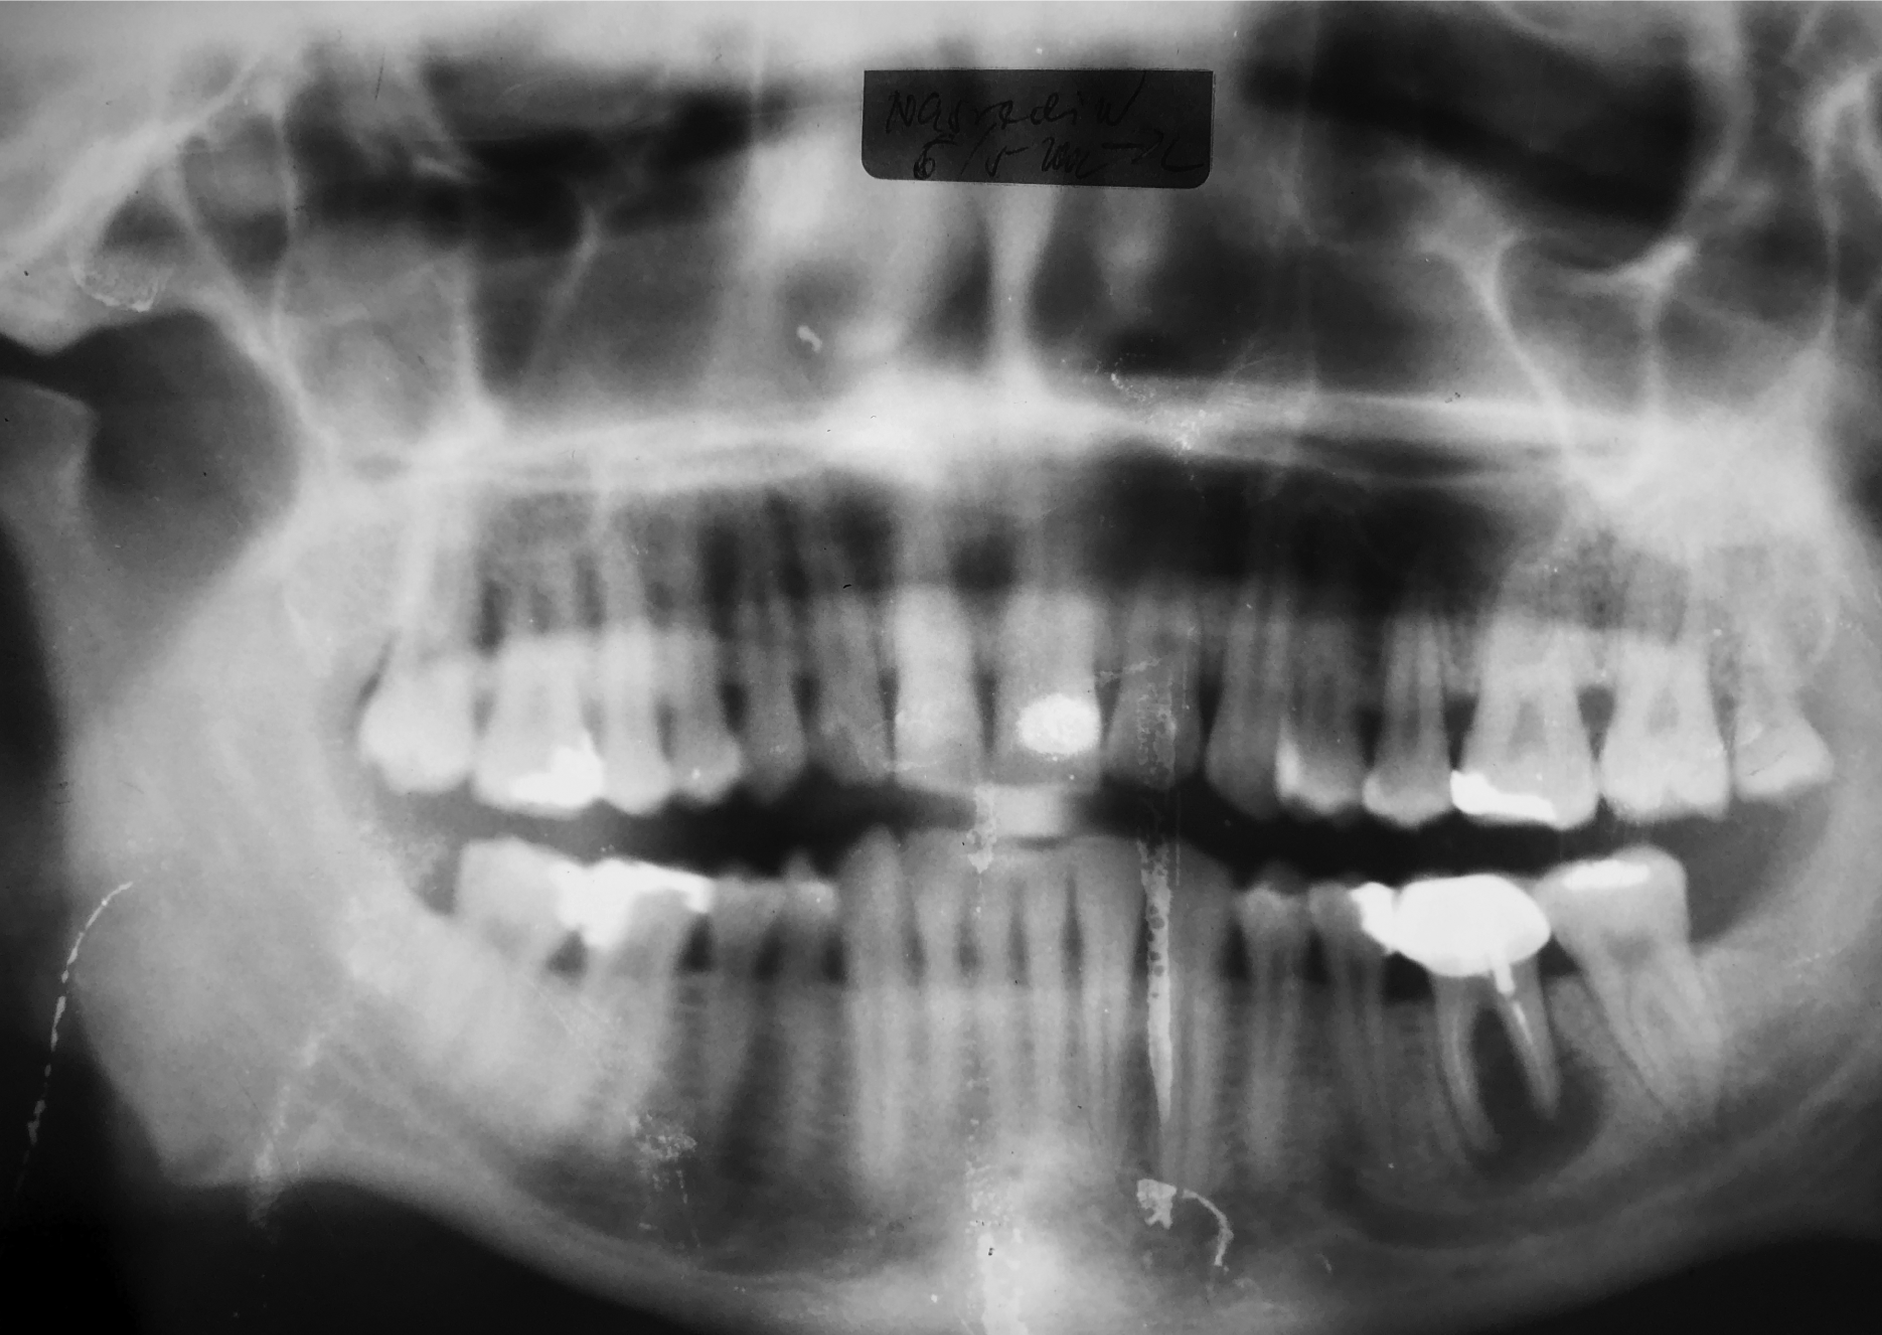

At the 10-year recall in April 2013, the prosthetic restoration was still fully functional, and the peri-implant tissues remained healthy.